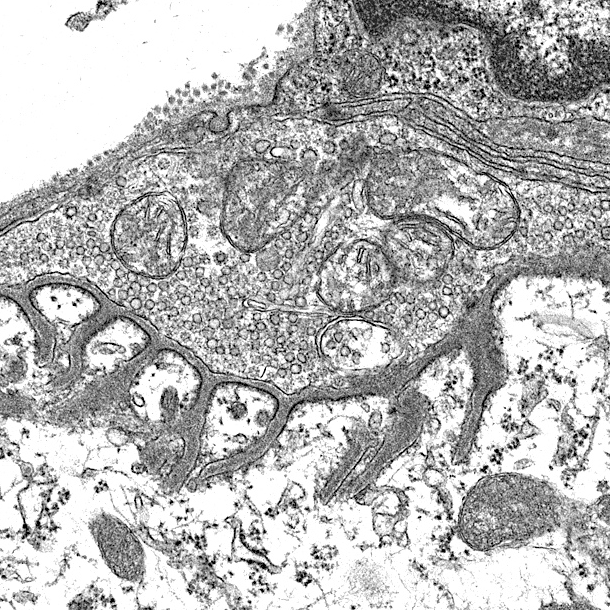

Figure 1. Synapses are fundamental, functional units of the nerve system, which signals are transduced from a neuron to its target neuron or cell.

Efficient transmission of signals from motor neurons to muscles is guaranteed by delicate structures of the NMJ. For example, the active zones are precisely aligned with the shoulders of junctional folds of muscle membranes where AChRs are packed (Figure 2). NMJs are mostly localized in the middle of muscle fibers, 1 per muscle fiber and occupy less than 0.1% of the surface area of muscle fibers.

Figure 2. Barik’s EM and Lei Li’s diagrams. (label pre- and post-synaptic structures)